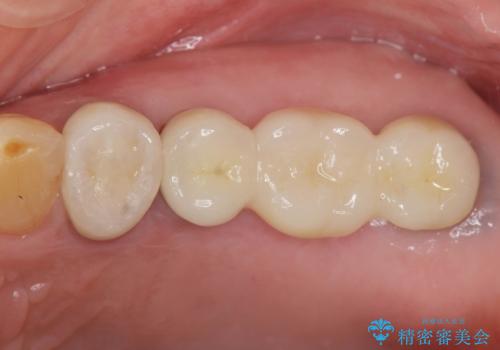

- 奥歯を虫歯で失ってしまい、しっかりと噛めるようになりたい、と希望され来院されました。

3本の歯(クラウン)を2本のインプラントで支えるインプラントブリッジによる咬合機能の回復を計画します。

治療後、しっかりと咬合機能が回復され見た目の自然さにも満足いただくことができました。